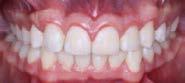

En la fotografía de frente (Figura 11) se ve la sonrisa armónica, la corrección de la línea media dental superior e inferior respecto a la línea media facial, en la de perfil final (Figura 12) se mantuvo el perfil labial. El tiempo de tratamiento activo fue de 2 años y 3 meses.

En la Figura 13 se muestra líneas medias dentales superior e inferior coincidentes, se obtuvo clase II molar funcional bilateral y clase I canina izquierda y derecha con el OD 14, la correcta adhesión del trasplante conformado como carilla en la cara vestibular del OD 13, oclusión funcional, overjet y overbite adecuados.

Se observa la liberación del apiñamiento superior e inferior, ( Figura 14) se incluyó el OD 13 al arco y se consiguió la forma oval de ambas arcadas.